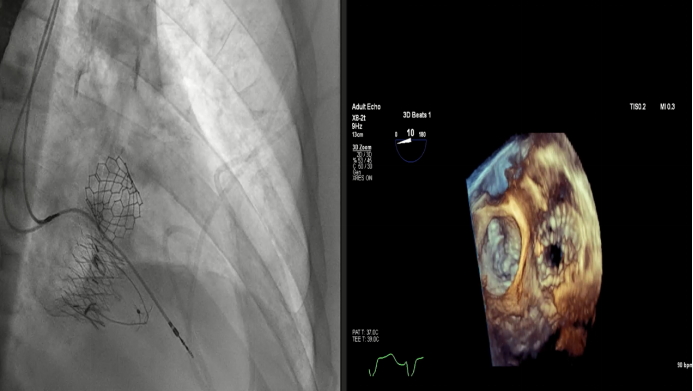

Dee Dee Wang教授分享了Henry Ford Hospital前4例Lux-Valve Plus的植入經(jīng)驗,并提示術(shù)中確定瓣葉夾持鍵的位置處于三尖瓣瓣環(huán)下方(右心室側(cè)),以及室間隔固定片與室間隔的相對位置關(guān)系是最關(guān)鍵的兩個步驟。使用經(jīng)胃底短軸切面,有時配合右室流入/流出道切面的X-plane就能較容易地獲取相關(guān)影像。由于Lux-Valve Plus對超聲影像的要求較低,手術(shù)過程會相對比較流暢。